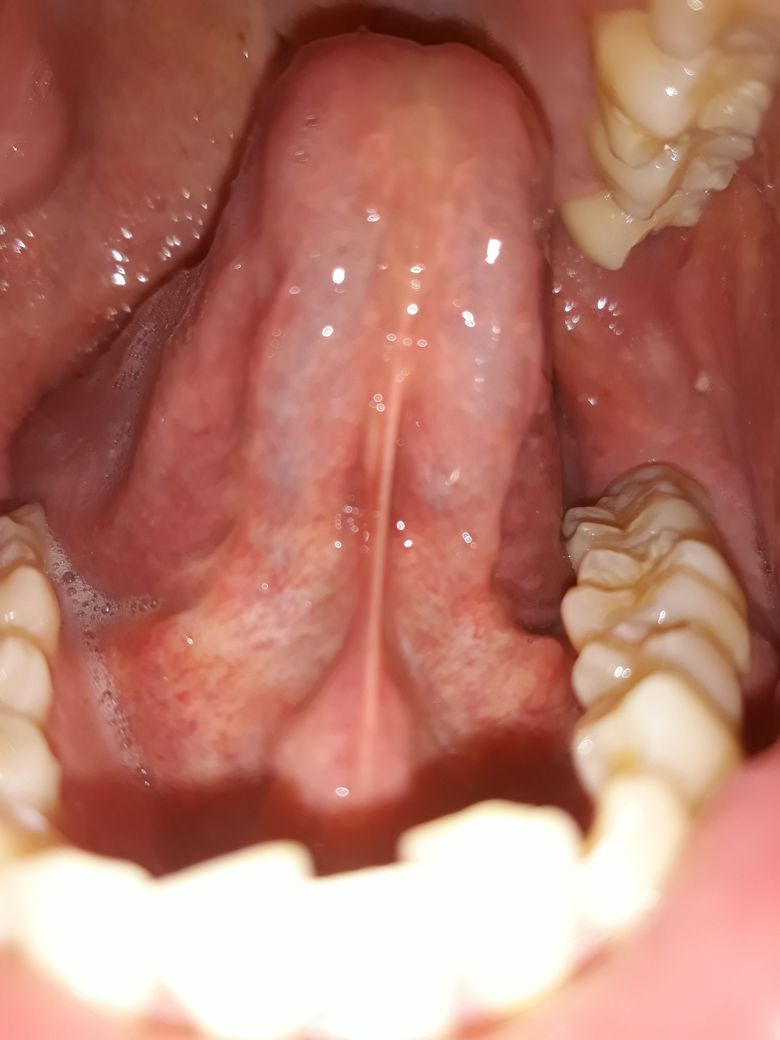

혓바닥 아래 상태가 정상인가요???

양치하다가 혓바닥 옆쪽 아래를 봤는데 잔핏줄도 많이 보이고 중간에 색깔도 군데군데 누런거같기도한데 만져보니깐 부드럽고 통증이나 불편한건 없습니다. 괜찮은건가요?

• 2번 째 사진

입 구석구석을 살펴보셨네요. 사진 올려주신 것만 봐서는 특별한 이상은 없어 보입니다. 증상도 없으니 괜찮다고 보셔도 되구요.